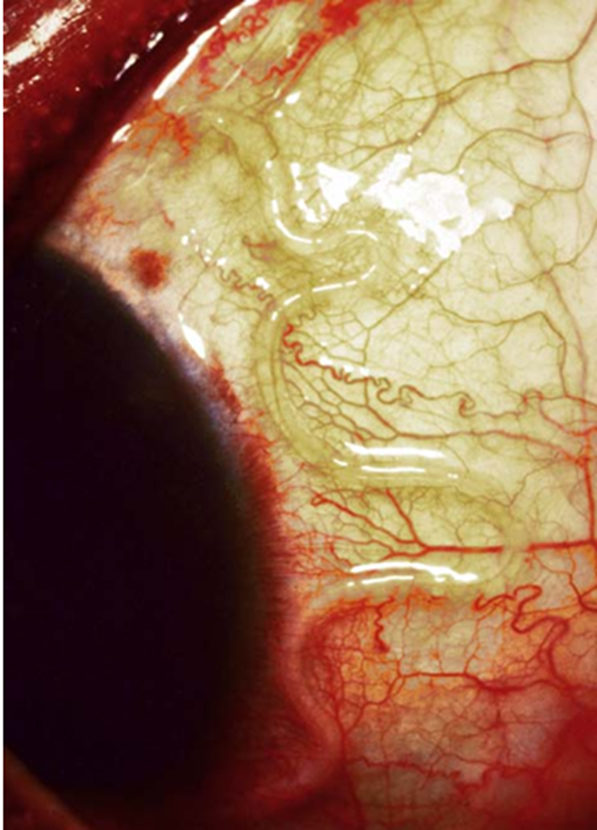

African eyeworm, Loa loa. Adult filarial nematode just beneath conjunctiva of human eye

• Ocular: Keratitis, chorioretinitis, eventual blindness